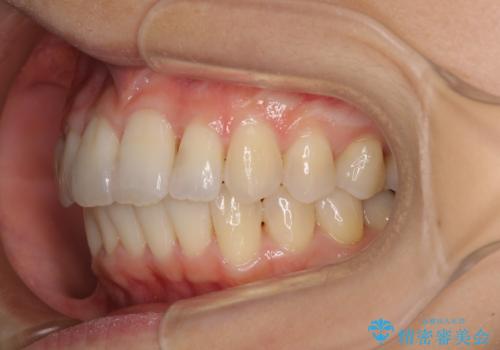

短期間で仕上げたい ワイヤーでの非抜歯矯正

- 前歯の捻れと、それに伴う口元の突出感を気にして来院された患者様です。

早く治療を終えたいとのことで、ワイヤー装置による矯正治療を行うこととしました。

上顎前歯の叢生が解消されると出っ歯になることが分かっていたので、両側奥歯付近にアンカースクリューを入れ、出っ歯を改善するためのゴムかけを行いました。

ゴムかけを頑張っていただいたので、当初の予定通り、1年強で治療を終えることができました。